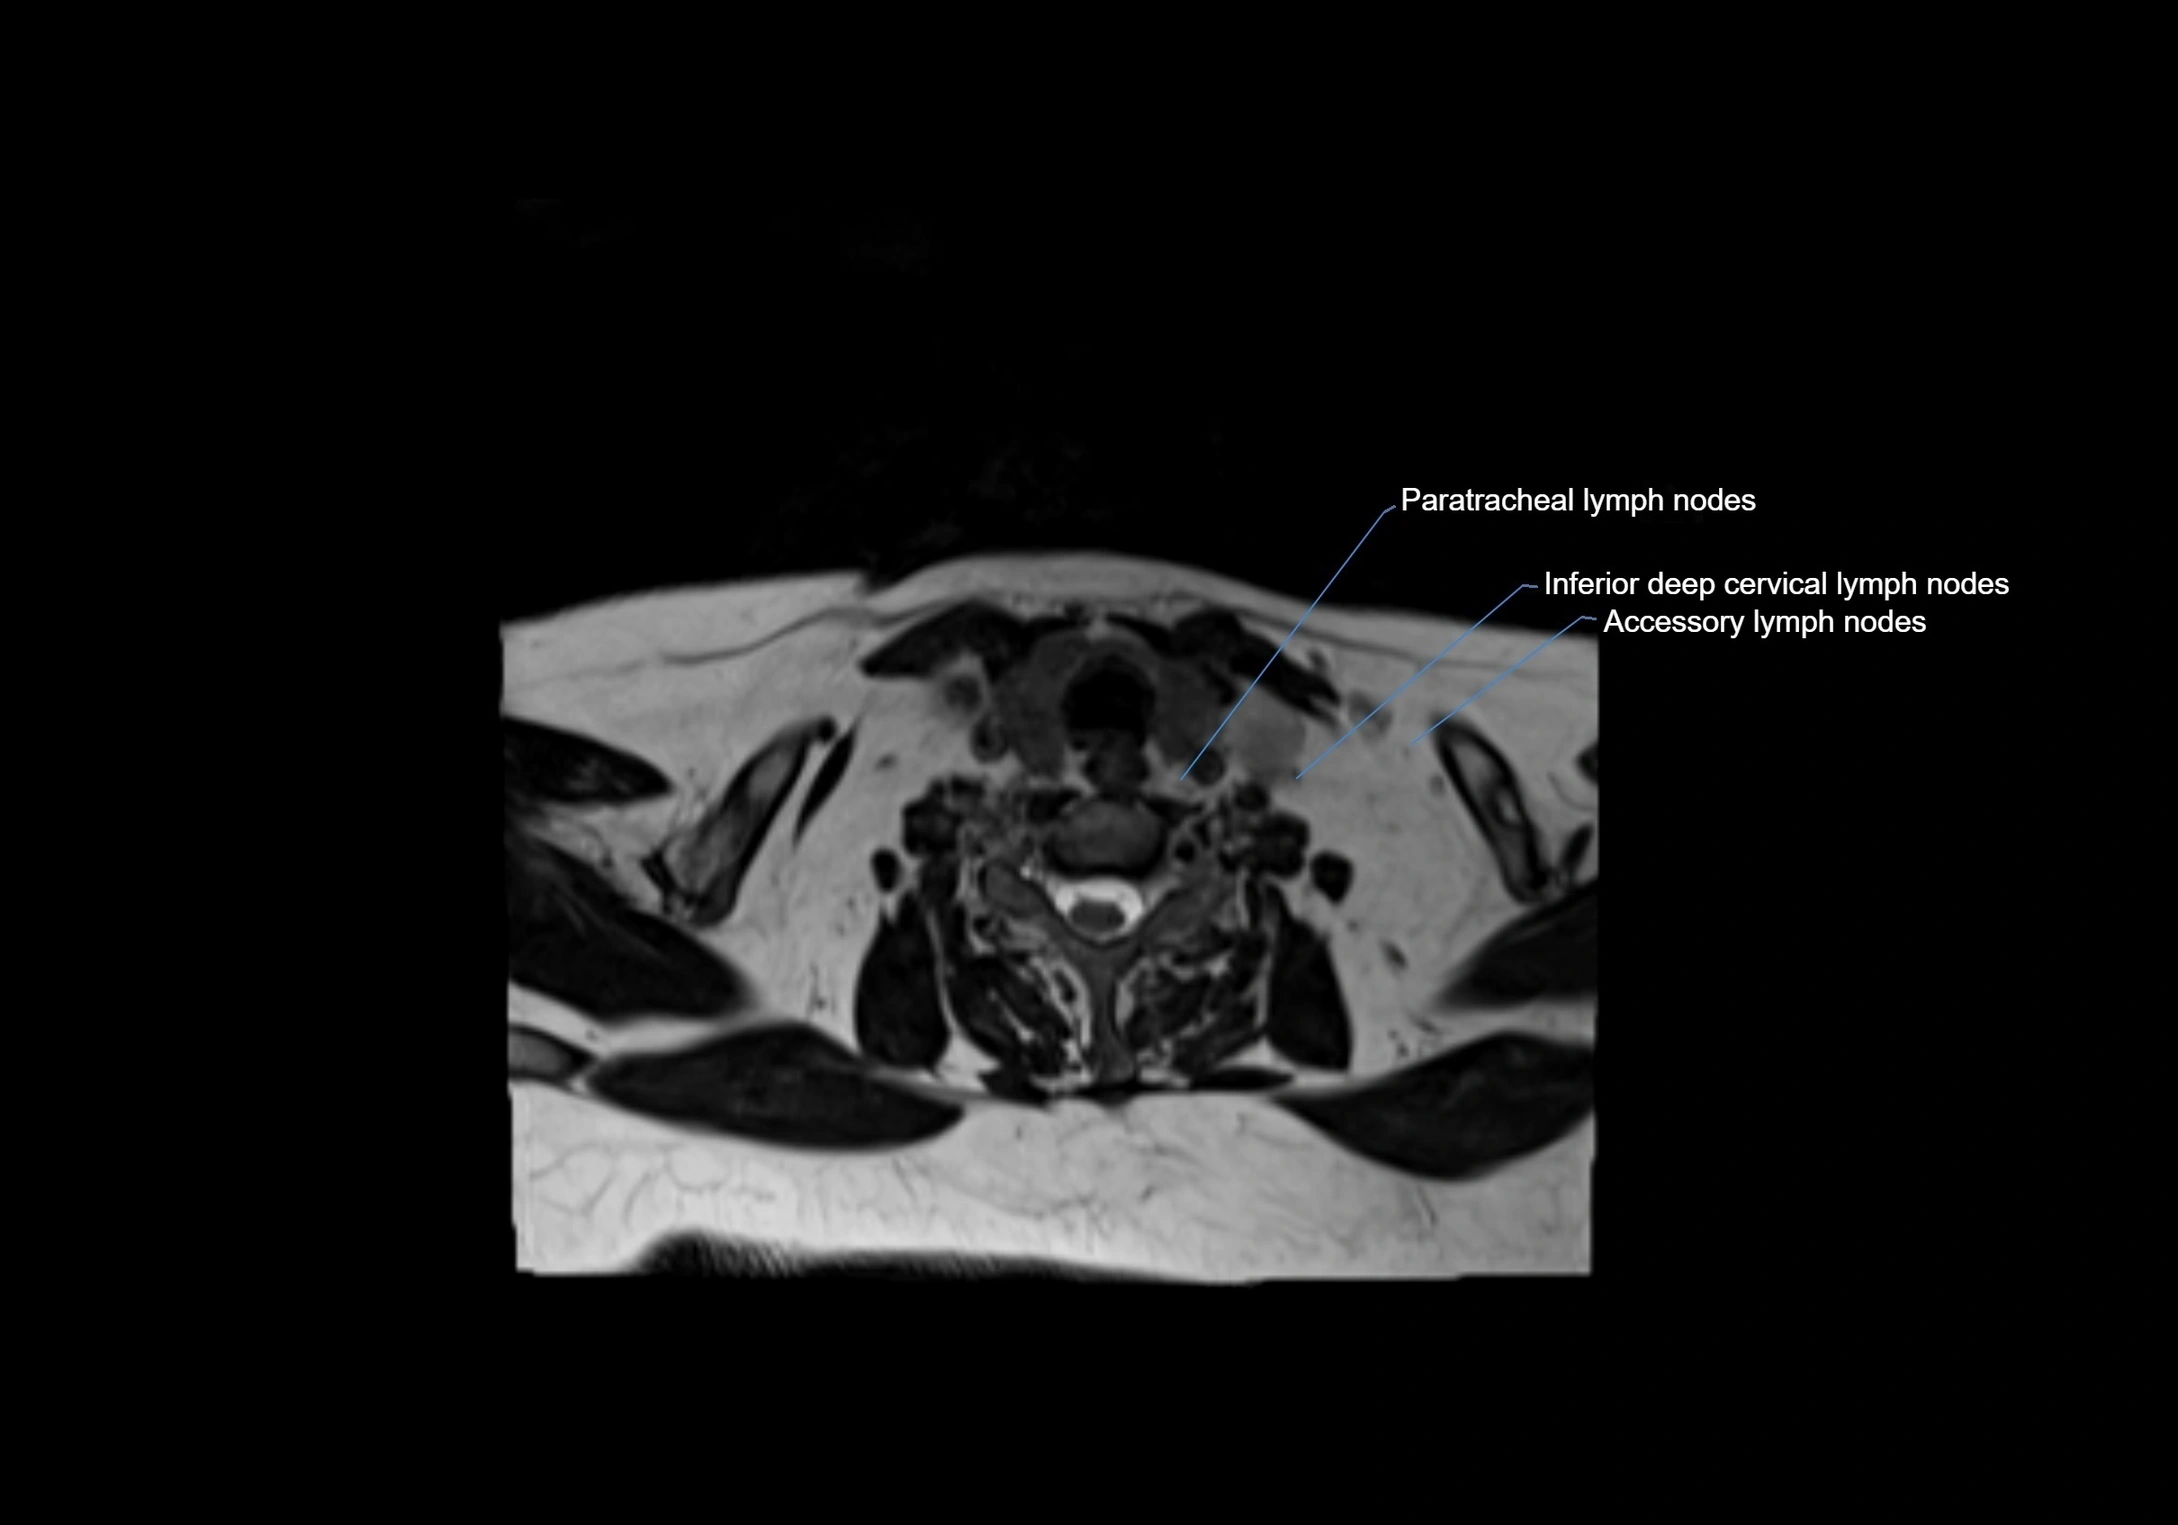

Location

• Found along primary lymph node chains, including preauricular, submandibular, parotid, and occipital regions

• Embedded in subcutaneous fat or superficial fascia, often lateral or posterior to primary nodes

MRI Appearance

T1-weighted images:

• Normal accessory nodes appear as small, oval hypointense to intermediate signal structures within subcutaneous fat

• Surrounded by hyperintense fat, enhancing contrast for visualization

• Pathological nodes may appear enlarged or rounded, sometimes with cortical thickening

MRI images

image